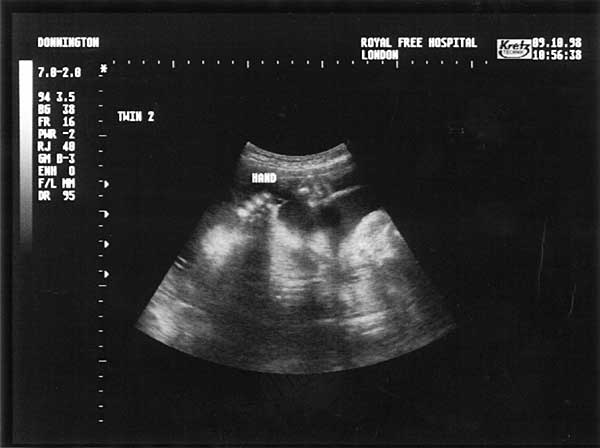

28 Weeks - Friday 9th October 1998.

Twenty Eight Week Scan 3